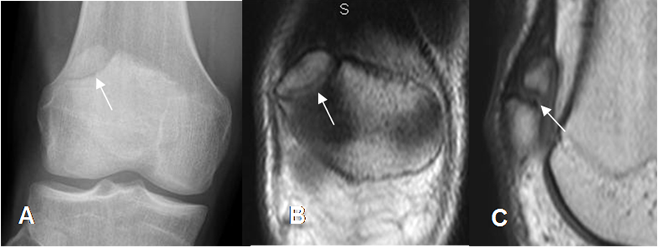

Fig 50. Patela bipartita.

A: Rx AP de rodilla. Fragmento supero-externo en la patela de bordes escleróticos, por variante bipartita.

B: RM coronal en T1 y C: RM sagital en T1. Iguales hallazgos a los descritos en la Rx simple.